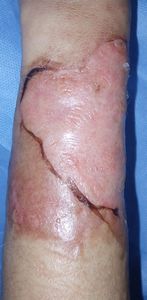

48歳女性。

12月7日夜,自宅でコーヒーのドリッパーが倒れて左前腕に熱傷受傷。直ちに〇〇外科クリニックを受診。12日まで通院していたが,夕方17:00で受付が終了するため,18:00時まで開いている△△皮膚科クリニックにした。深いヤケドであり治るかどうかわからないと説明されたため,不安になりネットで調べて当科を受診。

当科ではプラスモイスト(R)で治療。

| 2013年12月18日 | 12月26日 | 2014年1月10日 |

当科初診時の状態は「上皮化寸前」,つまり「治癒寸前」である。それなのに上記の△△皮膚科クリニックの先生には「深いヤケドで治るかどうかもわからない」と映ったらしい。ヤケドの治療をしたことがない皮膚科の先生なんでしょう。